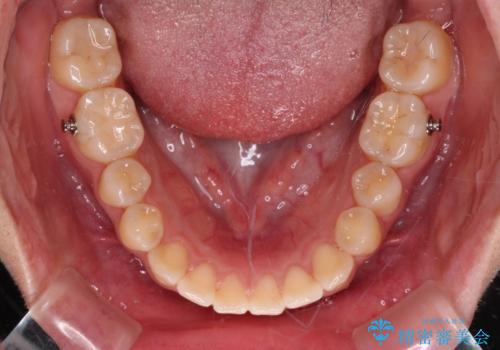

- 上下の前歯が非接触であることと、それに伴う口元の閉じにくさを気にして来院された患者様です。

奥歯の咬み合わせを見ると、上顎が下顎に対して相対的に前方にありました。

口元の閉じにくさを改善するためには、上顎臼歯を後方に移動させた咬み合わせにする必要があります。

インビザライン単体で改善することも可能ですが、達成する可能性が高くないため、カリエールディスタライザーという補助装置を併用して、より確実性を上げることとしました。

奥歯の咬み合わせを改善しながら、並行してインビザラインで歯列を整えることとしました。

カリエールディスタライザーを併用したことで、確実かつ短期間で治療を終えることができました。